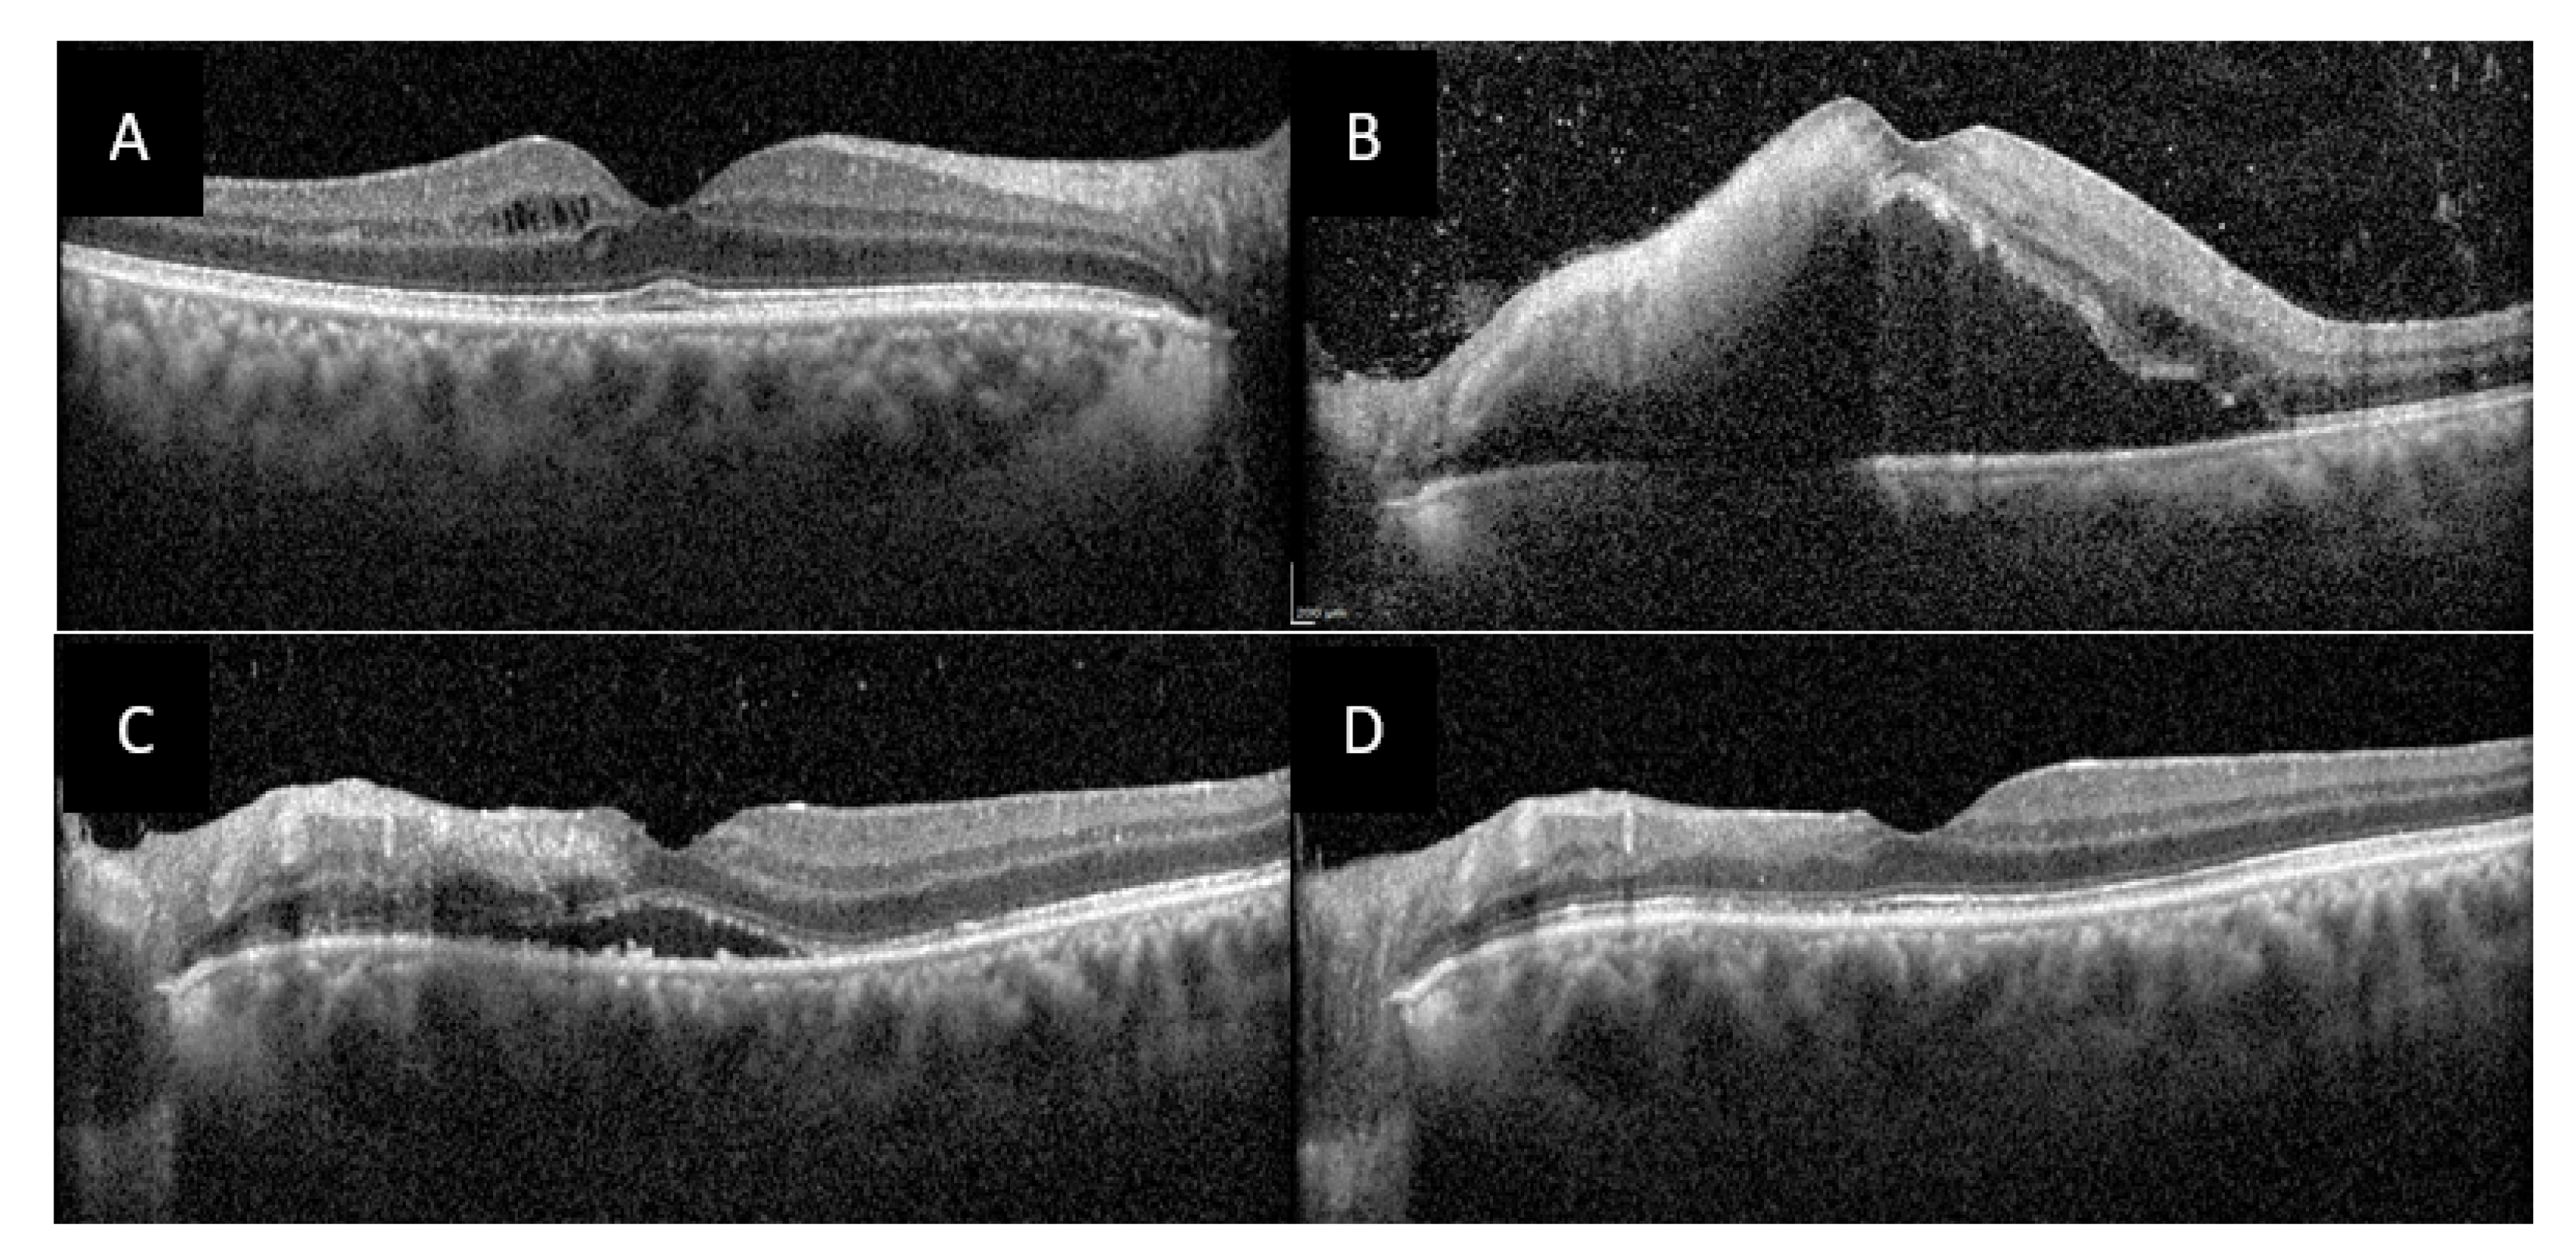

OCT of the right macula found mild intraretinal edema (Figure 4A) and in the left macula there was a large serous retinal detachment, a nodule of intraretinal hyper-reflectivity with loss of differentiation of the inner retinal layers at the site of retinal necrosis, as well as intraretinal edema, and hyperreflective dots in the vitreous (Figure 4B).

Initial treatment comprised intravenous acyclovir pending the results of anterior chamber tap. Upon negative results, methylprednisolone pulses were administered over three days followed by slow tapering with oral corticosteroids and treatment with azathioprine and infliximab. Colchicine was also started in prevention of recurring oral ulcers. The ophthalmologic signs rapidly decreased with complete regression of AU, vitritis, macular edema (Figure 5C) and vasculitis at 1 month, and persistence of a mild bilateral papillitis and retinal scarring in place of the necrosis nodule in the left eye at 3 months follow-up (Figure 5D). At last visit 6 month later there had been no relapse in uveitis or oral ulcers.